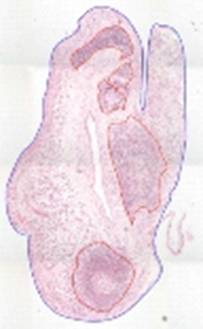

Synovial tissue is obtained using an ultra-sound guided needle biopsy or arthroscopic approach (forceps). Excess synovial fluid is obtained by needle aspiration. Synovial cellular phenotypes (B/T cells, plasma cells, macrophage cells and FDC) and lymphoid organisation are determined by immunohistochemistry (IHC) and digital image analysis. Biopsies are classified according to the aggregational tendency and typical features of secondary lymphoid organs. Blood samples are also routinely obtained as part of complete study set.